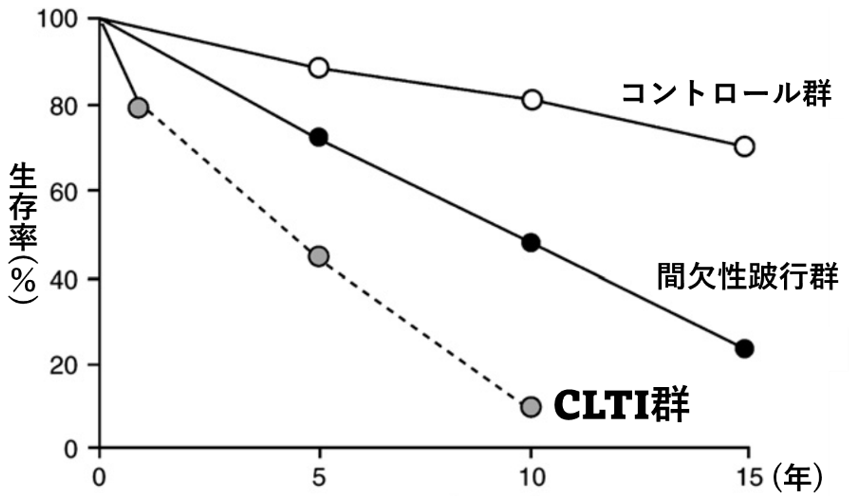

下肢閉塞性動脈硬化症を発症した方の約3割は冠動脈疾患や脳動脈疾患を合併しているといわれており注意が必要です。一般的には1.無症状⇒2.歩いたときに足が痛くなる、一度に歩ける距離が短くなる⇒3.じっとしていても足が冷たく痛くなる⇒4.足に出来た傷が治らない、黒く変色して拡大する、という順に進行しますが、糖尿病患者さんや透析患者さんの中にはいきなり4.で発症する方もいます。3.4.を重症下肢虚血(CLI:critical limb ischemia)あるいは包括的高度慢性下肢虚血(CLTI:chronic limb-threatening ischemia)とよび、治療しなければ1年で20%以上が命を落とす非常に危険な状態です(図2)。

図2:Eur J Vasc Endovasc Surg Vol 33,

Supplement 1, 2007より改変